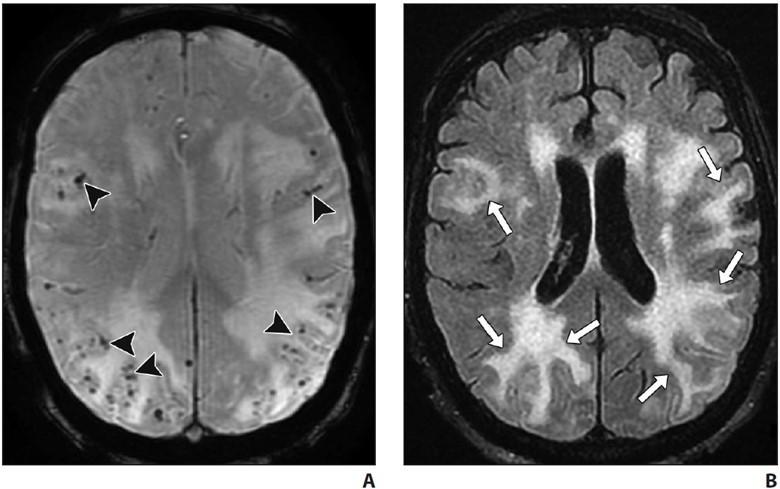

Deposition of amyloid-β in the media and adventitia of cerebral cortical and leptomeningeal vessels is the hallmark of cerebral amyloid angiopathy (CAA). The amyloid deposition weakens the vessel wall, leading to rupture and hemorrhage. On imaging, this manifests as a spectrum of foci of intraparenchymal lobar hemorrhage, convexal subarachnoid hemorrhage, and cortical and subcortical microhemorrhages. Areas of superficial siderosis are seen, indicative of prior subarachnoid hemorrhage. Subcortical white matter long-TR hyperintensities are typical of CAA differentiated from periventricular lesions seen in hypertensive cerebrovascular disease [35].

Acute inflammatory CAA may be seen on a background of chronic changes, in association with rapidly progressive cognitive decline [36]. On imaging, inflammatory CAA is seen as solitary or multifocal areas of confluent white matter hyperintensity with or without mass effect or patchy areas of enhancement and is often centered around foci of microhemorrhage [36] (Fig. 7).

A and B, Axial susceptibility-weighted (A) and FLAIR (B) MR images in patient presenting with progressive cognitive decline. Numerous widespread foci of chronic microhemorrhage (arrowheads, A) are associated with confluent areas of vasogenic edema (arrows, B) suggesting inflammatory cerebral amyloid angiopathy. Areas of edema resolved with steroid therapy.

A fatal prion disease, CJD presents with rapidly progressive dementia, along with myoclonus, pyramidal, extrapyramidal, and cerebellar signs. CJD is mostly sporadic, but it can be familial, infectious (variant CJD), or iatrogenic. There is spongiform degeneration and gliosis. The MRI sequence with the highest sensitivity and specificity is DWI, which shows the characteristic imaging finding of hyperintensity of the basal ganglia, thalami, and the cortical regions [38, 39] (Fig. 8).

A–C, Axial diffusion-weighted MR images of patient presenting with rapidly progressive cognitive decline show signal abnormality in bilateral corpus striatum (arrowheads, A and B), thalamic pulvinar (arrows, A) and scattered cortical gyriform reduced diffusion (arrowheads, C). Hockey-stick configuration of dorsomedial and pulvinar involvement is commonly described with Creutzfeldt-Jakob disease.

Symmetric involvement of the posterior thalami (pulvinar sign) and the dorsomedial nuclei (hockey-stick sign) is common in variant CJD but can also be seen in sporadic CJD. Bilateral but asymmetric involvement of the cortical areas is seen [38, 39]. Enhancement is uncommon. Definitive diagnosis may require brain biopsy. Death ensues in a few months.